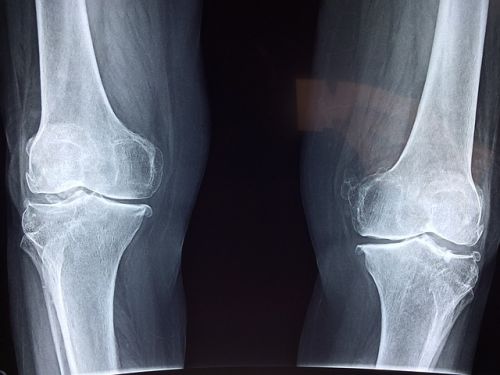

그 외에도 혈액 검사로 요산 농도를 측정하고, X선이나 초음파, CT 등의 영상 검사로 관절 손상과 통풍 결절을 확인할 수 있습니다. 급성 발작 시 혈중 요산 농도가 일시적으로 떨어질 수 있으니, 증상이 없을 때 검사를 반복하는 경우도 있습니다.

| 영상 검사 | X선, 초음파, CT로 관절 손상 및 결절 확인 |